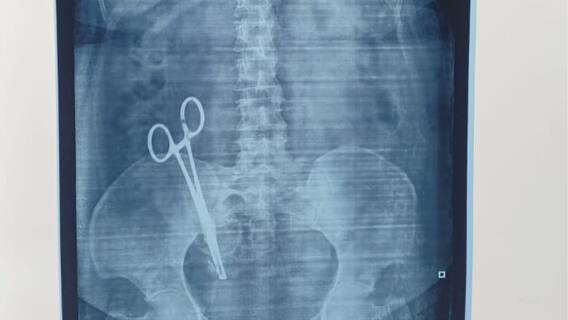

உத்தரபிரதேச மாநிலம் லக்னோவில் மருத்துவ அலட்சியம் காரணமாக ஏற்பட்ட அதிர்ச்சியூட்டும் சம்பவம் தற்போது வெளிச்சத்திற்கு வந்துள்ளது. அறுவை சிகிச்சைக்குப் பிறகு 17 ஆண்டுகளாக ஒரு பெண் தன் வயிற்றில் சுமந்து கொண்டிருந்த, அறுவை சிகிச்சை கத்தரிக்கோல் அகற்றப்பட்டுள்ளது. சந்தியா பாண்டே தனது குழந்தையின் பிரசவத்தின்போது பிப்ரவரி 28, 2008 அன்று 'ஷி மெடிக்கல் கேர்' நர்சிங் ஹோமில் அறுவை சிகிச்சைக்கு உட்படுத்தப்பட்டார். அங்கு தான் இந்த மருத்துவ தவறு நடைபெற்றுள்ளதாக, பாதிக்கப்பட்டவரின் கணவர் போலீசாரிடம் புகாரளித்துள்ளார்.

சந்தியா எனும் பெண் பேறுகால அறுவை சிகிச்சைக்குப் பின்பு தொடர்ந்து வயிற்று வலியால் அவதிப்பட்டு வந்துள்ளார். பல ஆண்டுகளாக ஏராளமான மருத்துவர்களை சந்தித்தும், சந்தியாவின் உடல்நிலையில் சிறிதும் முன்னேற்றம் ஏற்படவில்லை. சமீபத்தில் லக்னோ மருத்துவக் கல்லூரியில் வழக்கமான மருத்துவ பரிசோதனையின் ஒரு பகுதியாக எக்ஸ்ரே எடுக்கப்பட்டது. அப்போது ​​அவரது வயிற்றில் கத்தரிக்கோல்க இருப்பது தெரியவந்தது. அப்போது தான் 17 ஆண்டுகளாக அவர் அனுபவித்து வந்த வலிக்கு காரணம் என்ன என்பது அம்பலமானது.

கத்திரிக்கோல்கள் இருப்பது உறுதியானதும் அந்த பெண் லக்னோவில் உள்ள கிங் ஜார்ஜ் மருத்துவப் பல்கலைக்கழகத்தில் (KGMU) அனுமதிக்கப்பட்டார். அங்கு மார்ச் 26 அன்று ஒரு சிக்கலான அறுவை சிகிச்சை மூலம் அவை வெற்றிகரமாக அகற்றப்பட்டது. KGMU செய்தித் தொடர்பாளர் சுதிர் சிங், இந்த சம்பவம் குறித்த விவரங்களை உறுதிப்படுத்தினார், இந்த நடவடிக்கை சவாலானது என்றாலும், இறுதியில் அது வெற்றி பெற்றது என்றும், சந்தியா டிஸ்சார்ஜ் செய்யப்பட்டு வீடு திரும்பியுள்ளார் என்றும் கூறினார்.